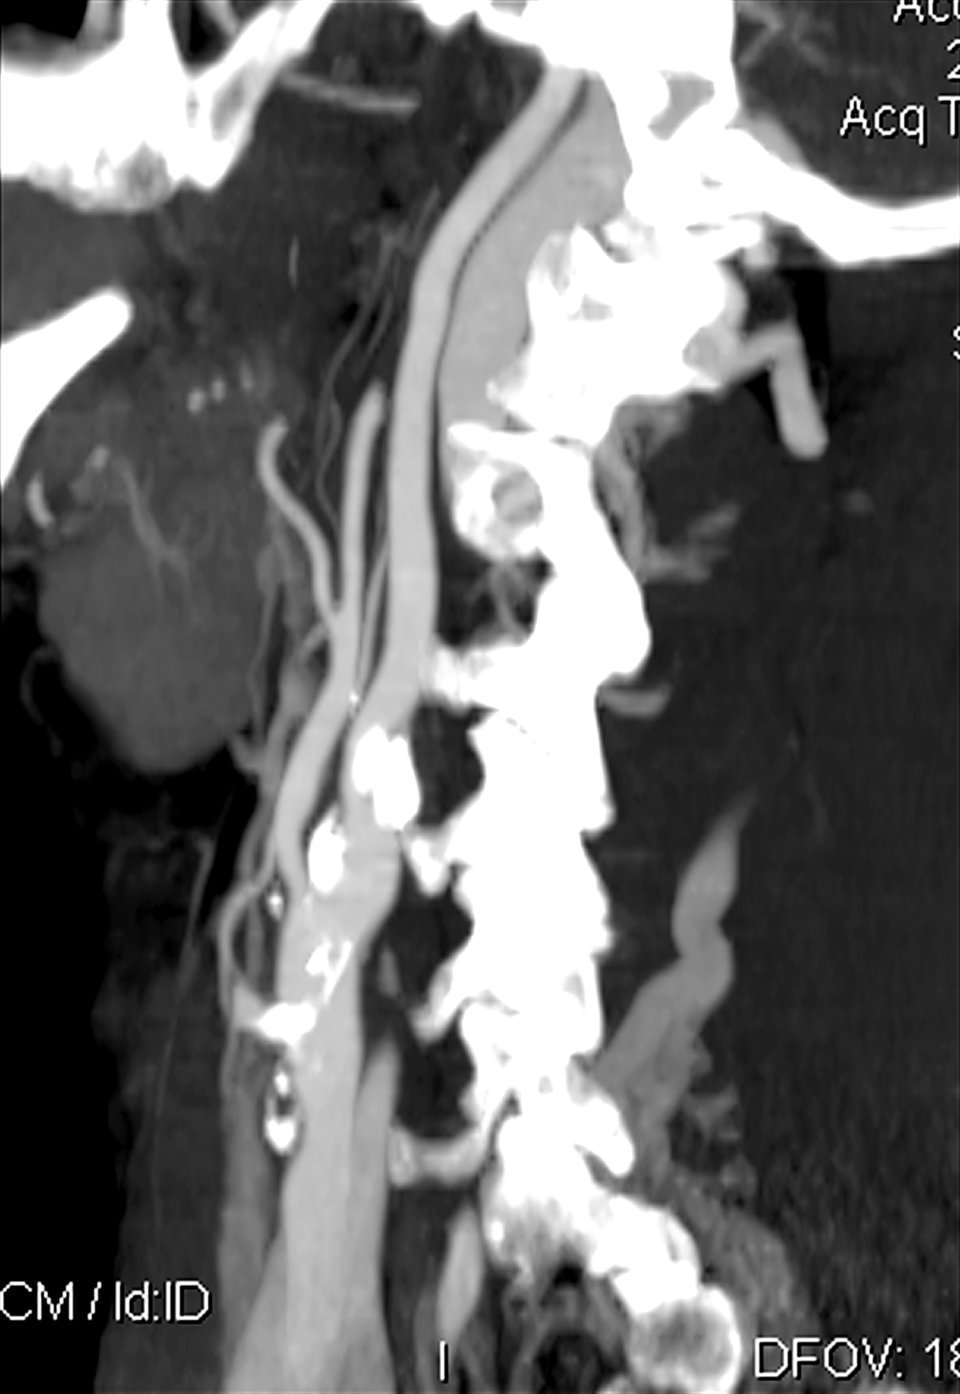

Im CT-Angiogramm sind im Bereich der Karotis arteriosklerotische Plaques (weiß) zu erkennen. Im CT-Angiogramm sind im Bereich der Karotis arteriosklerotische Plaques (weiß) zu erkennen. © mauritius images/Science Source/Neil M. Borden